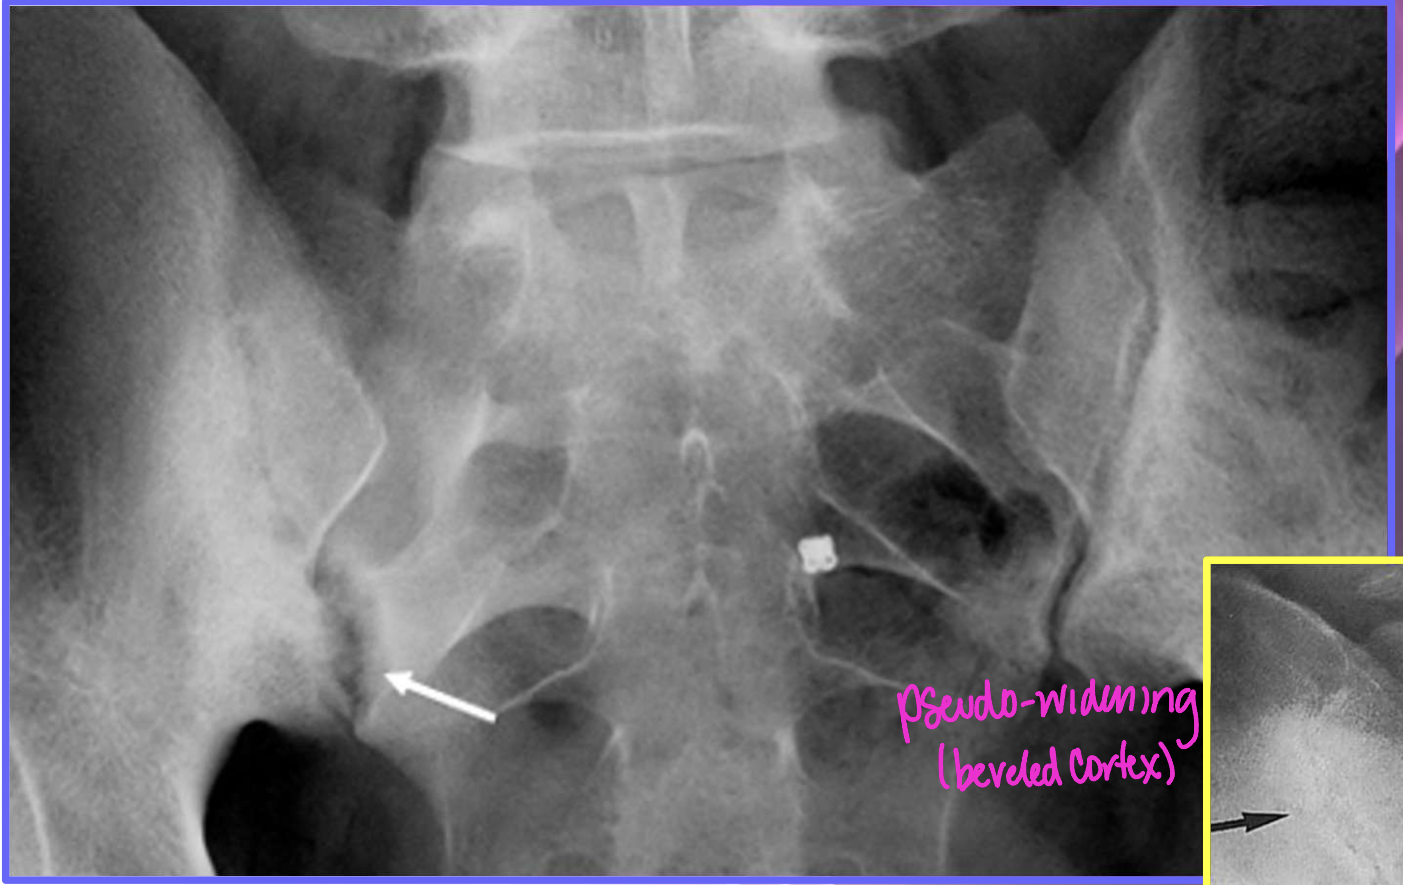

AS Sacroilitis grading

0 - normal SI joint width + sharp joint margins

1 - suspicious

2 - sclerosis, some erosions

3 - severe erosions, pseudo-dilation of joint space, partial ankylosis

4 - complete ankylosis

We can see JSN and subchondral sclerosis in OA, which feature of AS is not seen in OA

erosions!!